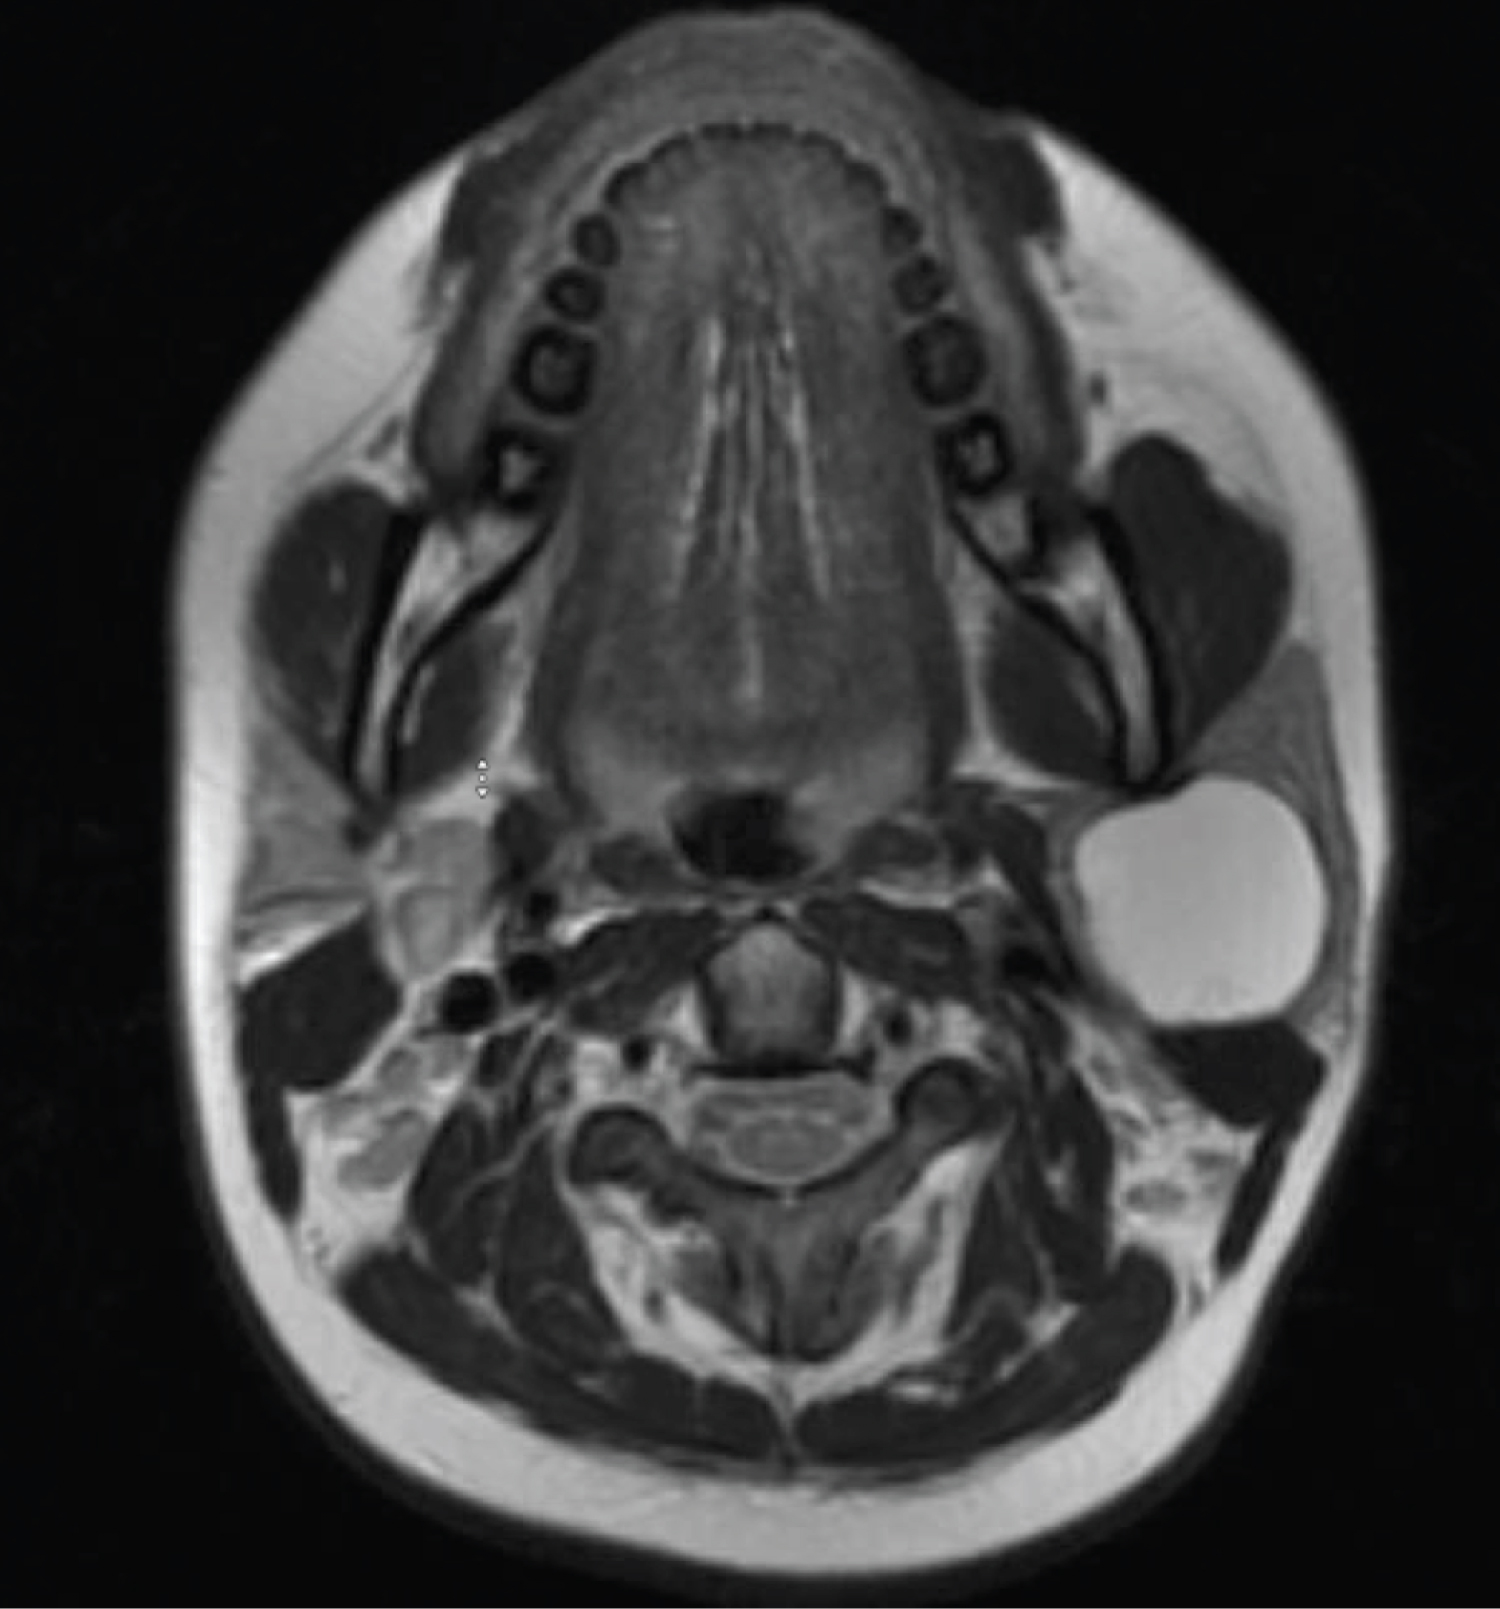

A 14-year-old girl with a history of migraine headaches, presents with progressively enlarging left parotid mass, present for at least 10 years. The patient reported associated swelling and erythema with concurrent viral infections. Denies facial numbness, weakness, pain, or hearing changes. While being evaluated for headaches, an MRI of the brain revealed a 3.7 × 3.1 × 3.0 cm T1 enhancing mass in left parotid gland (Figure 1 and Figure 2). On further work-up, a CT neck with contrast demonstrated a well circumscribed homogenous mass within the superficial lobe of the left parotid, which was read as likely a lipoma. Physical exam did not reveal any skin pits or depressions, no abnormalities of the EAC or of the tympanic membrane was seen on otoscopy. As the mass was slowly increasing in size, cosmetically concerning to the patient, and causing discomfort, the decision was made to proceed with surgery.

Figure 2: T1 axial MRI of parotid mass. View Figure 2